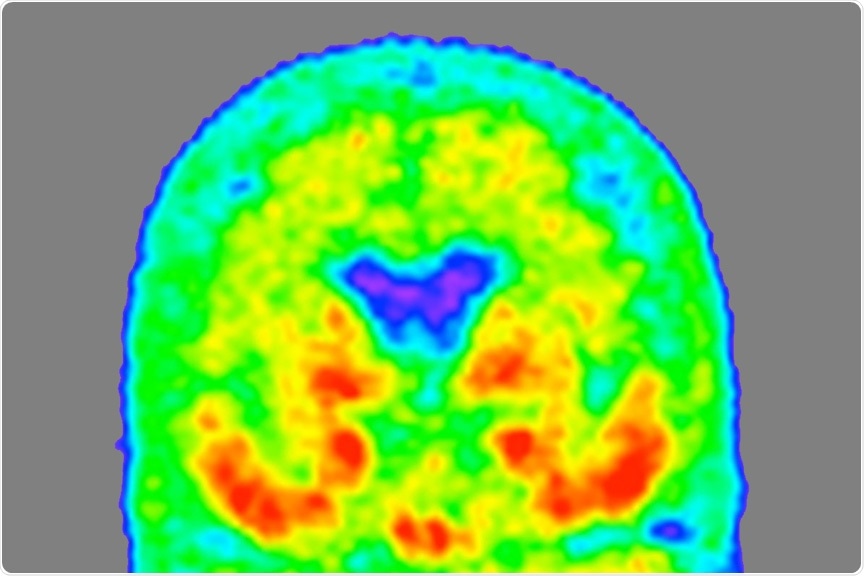

Heat map of tau

Image Credit: Tammie Benzinger/Knight ADRC